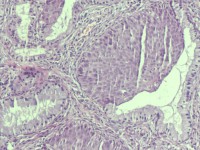

女

38岁

宫颈病变

宫颈癌筛查:HPV52(+)

宫颈6点组织

灰白色组织1块

HSIL(CIN3)累腺